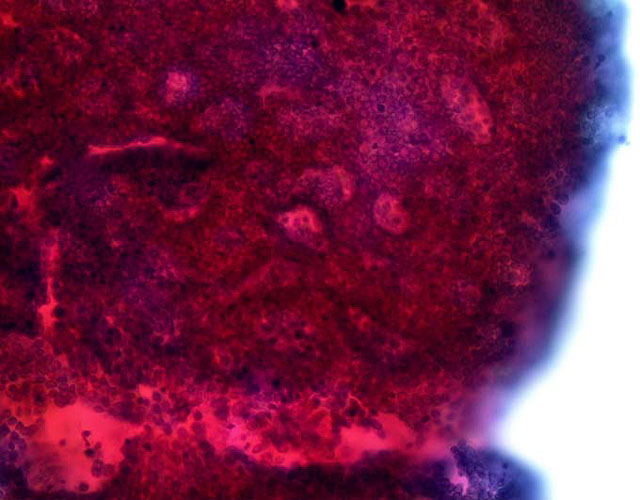

腺腔を多数伴う重積性集塊